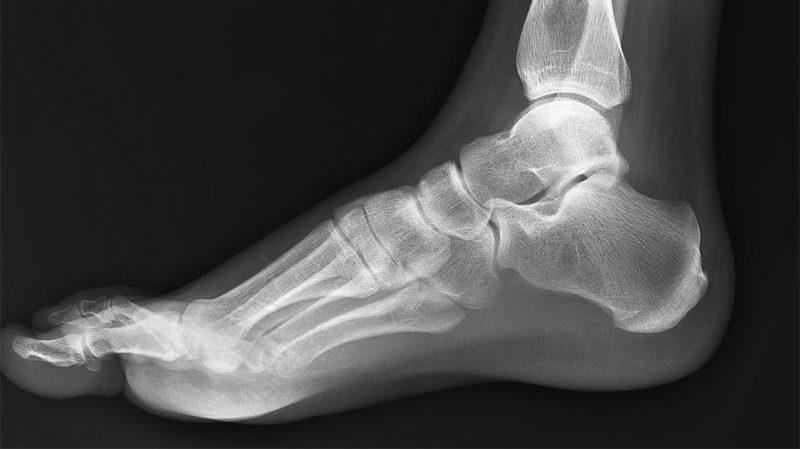

Для достижения наилучших результатов в лечении ортопед проводит ряд обследований, чтобы определить тип плоскостопия и степень его развития. Врачи до сих пор не пришли к единому мнению о необходимости лечения.

Как избавиться от плоскостопия, определяет лечащий врач, основываясь на индивидуальных особенностях пациента. Важно установить тип плоскостопия, так как именно он будет влиять на выбор хирургической методики.